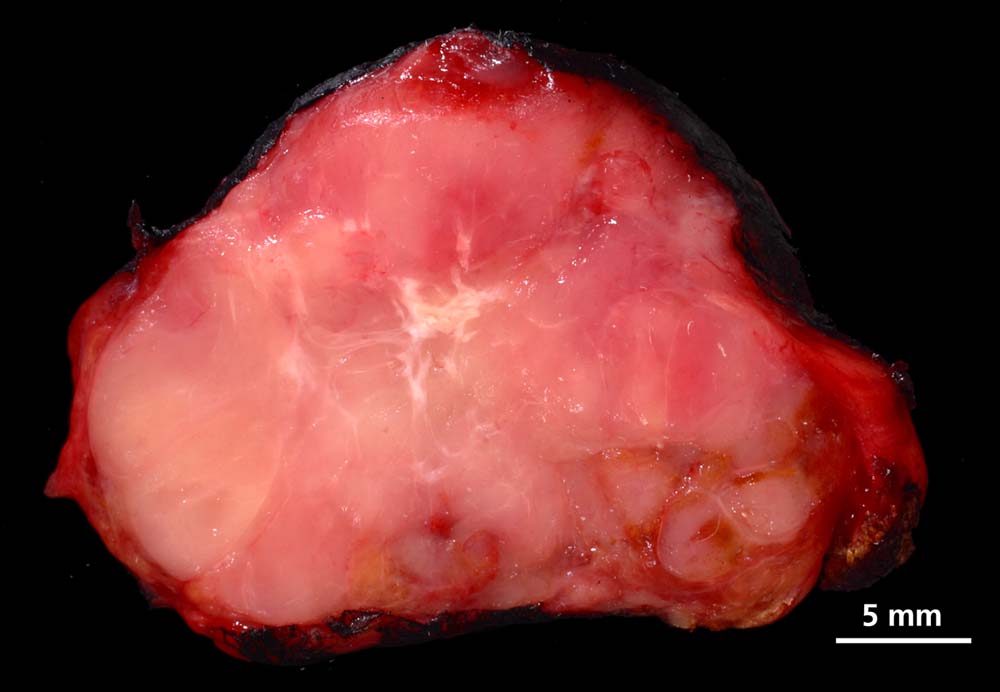

Die papillären Karzinome messen bei Diagnosestellung durchschnittlich 2.3cm und sind in bis zu drei Vierteln der Fälle multifokal. Makroskopisch sind die Tumoren blass, derb und unscharf begrenzt. Eine Kapsel liegt nur in 10% der Fälle vor. Papilläre Mikrokarzinome messen definitionsgemäss weniger als 1cm im Durchmesser und stellen häufige Zufallsbefunde in Strumektomien dar. Solche zufällig detektierten Mikrokarzinome haben bei Fehlen von histologischen Risikomerkmalen keinen Krankheitswert. Makroskopisch präsentieren sich Mikrokarzinome oft als grauweisse Narben.

Makroskopie

Befund

Pathologischer Befund

Normalbefund